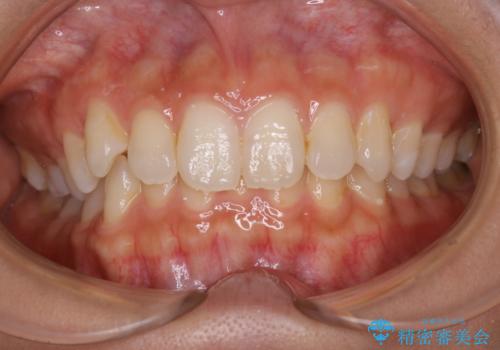

- 矯正治療を始める前に、歯のクリーニング希望とのことでした。

PMTC30分コースを行いました。

PMTCを行うことにより、スッキリと爽快感が得られたり、見た目も清潔感のある状態になるため、今後の治療などお口に対するモチベーションUPにも繋がります。